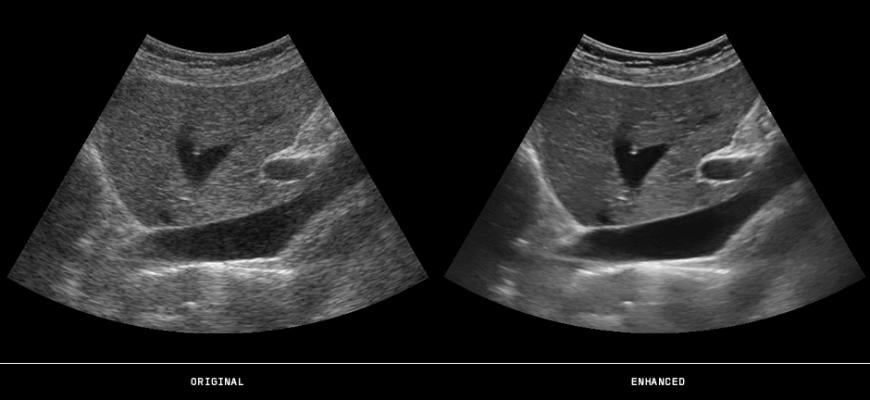

September 22, 2020 — Contrast-enhanced ultrasound (CEUS) helps physicians accurately diagnose some forms of liver cancer — and does so more safely and less expensively than computed tomography (CT) and magnetic resonance (MR), according to a report just published in Hepatoma Research.

“CEUS provides exquisite vessel resolution and is a completely non-invasive imaging option that produces the same information as CT and MR, which have historically been used to diagnose focal liver lesions,” according to Stephanie Wilson, M.D., head of the Department of Radiology at the University of Calgary and lead author of the report.

Citing the “unique benefits” of CEUS, Wilson noted that results are obtained in real-time and provide superior temporal resolution compared to other imaging modalities. In addition, CEUS is performed with a purely intravascular contrast agent that provides accurate images throughout all phases of the imaging process.